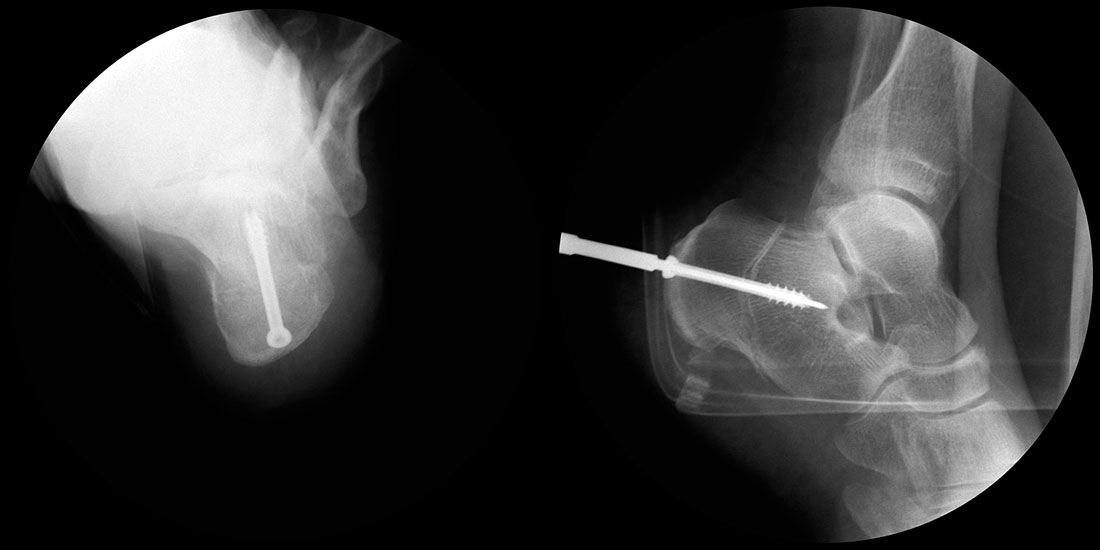

Operationsplanung anhand der Röntgenaufnahmen unter Beachtung wichtiger radiologischer Landmarks wie Rückfussachse, Metatarsale I – Talushals-Achse im dp und lateralen Strahlengang (Abbildung 1 und 2).

Abbildung 1

Abbildung 2